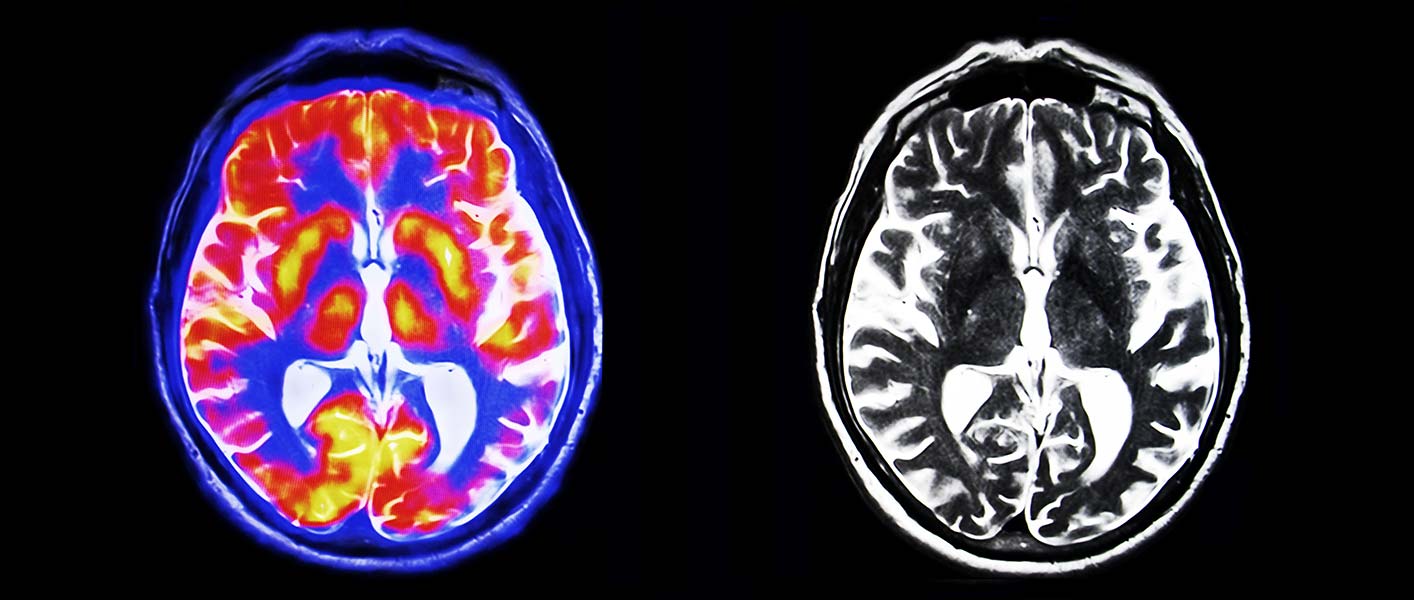

Demenz: Kognitiver Abbau Lässt Sich Mit Dem MRT Vorhersagen

www.medical-tribune.de